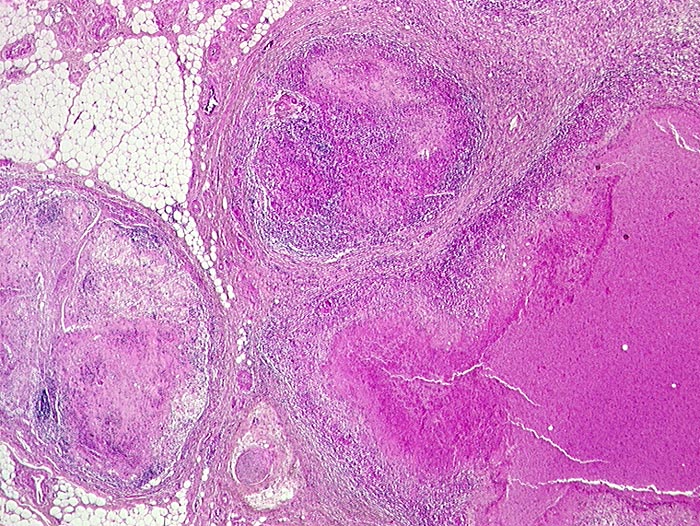

PathoPic ID 264 - Atypische Mycobakteriose

Atypische Mycobakteriose

Entzündung infektiös

Lymphknoten, abdominal

Lymphatische Gewebe, KM, Milz

Ausgedehnte käsige Nekroseherde in mesenterialen Lymphknoten.

Nachweis von säurefesten Stäbchen (Mycobakterium avium intracellulare) in den Nekrosen.

AIDS. HIV Positivität bekannt seit 2 Jahren bei iv Drogenabusus.

Histologie